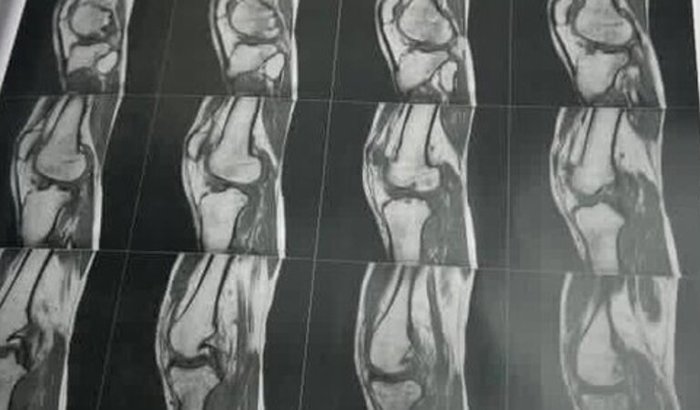

Eu sou Alex Andrio mingotti tenho 28 anos … trabalho como motoboy faz 3 anos na cidade de Caçador SC, A cerca de 2 mêses sofri um acidente no trabalho aonde vim bater meu joelho no meio fio… passou uns dias fui descer da cama e torci meu joelho,aonde acarretou uma série de problemas pois tive Ruptura ligamentar parcial de alto grau no ligamento cruzado anterior, ruptura do corpo/corno posterior do menisco medial e do menisco lateral, edema óssea de aspecto contusional nos condilos femorais e platôs tibiais…